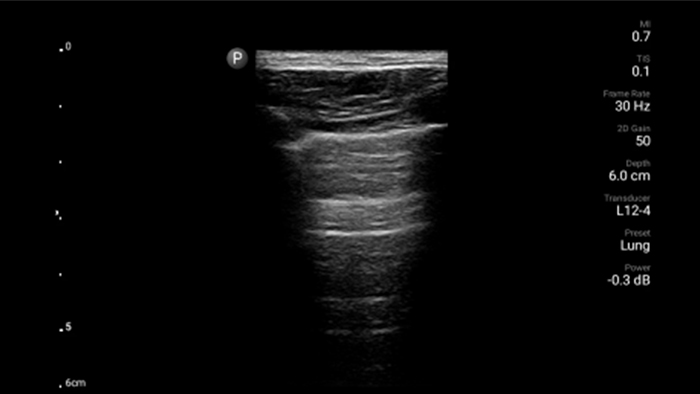

Utilice Lumify para la evaluación de las vías respiratorias y pulmonares

Las soluciones Lumify POCUS pueden ayudarle a detectar el tubo endotraqueal dentro de la tráquea, ayudar en los procedimientos de cricotirotomía emergentes, en el diagnóstico de derrame pleural y enfermedades alveolares intersticiales.

• Rango extendido de frecuencias de operación de 4 a 1 MHz • 2D, Doppler a color, Modalidad M, XRES avanzado e imágenes armónicas multivariables • Imagenología de alta resolución para aplicaciones abdominales y cardíacas: optimizaciones de preajustes de imágenes cardíacas, gineco-obstétricas, pulmonares, abdominales y FAST.